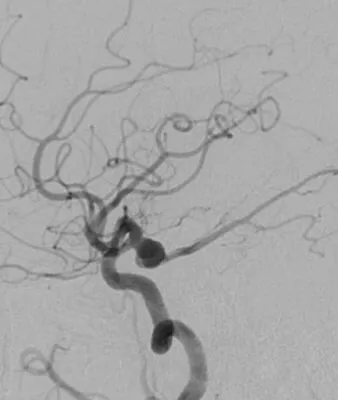

男,49岁,蛛网膜下腔出血

左侧后交通动脉瘤,胚胎型大脑后动脉

3D

局部观,宽颈,涉及颈内动脉和后交通动脉

椎动脉造影见左侧大脑后动脉P1段很细